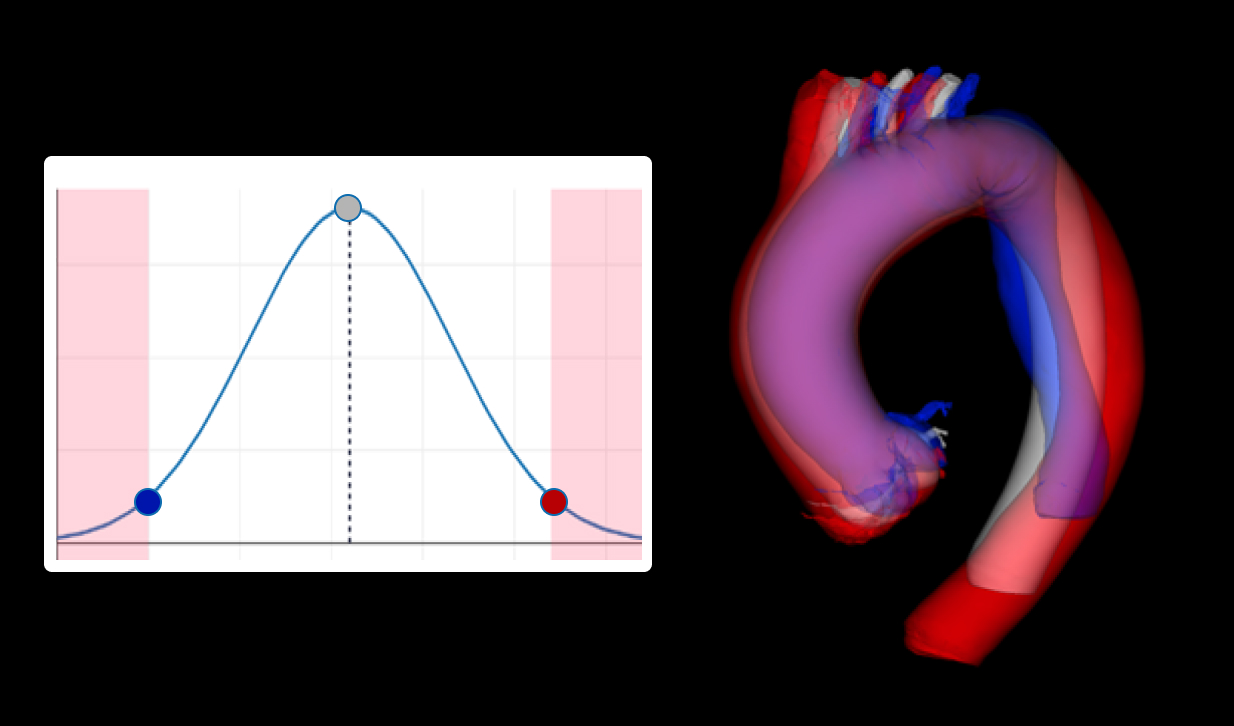

Anatomy study02

Better understand your target anatomy with the help of virtual models, morphological and statistical analysis and simulations.

Visualize your device in highly-accurate anatomy models of humans and animals, prior to manufacture.

Simulate your device in the entire virtual target population to investigate how these body variations may affect the performance and safety of your device.